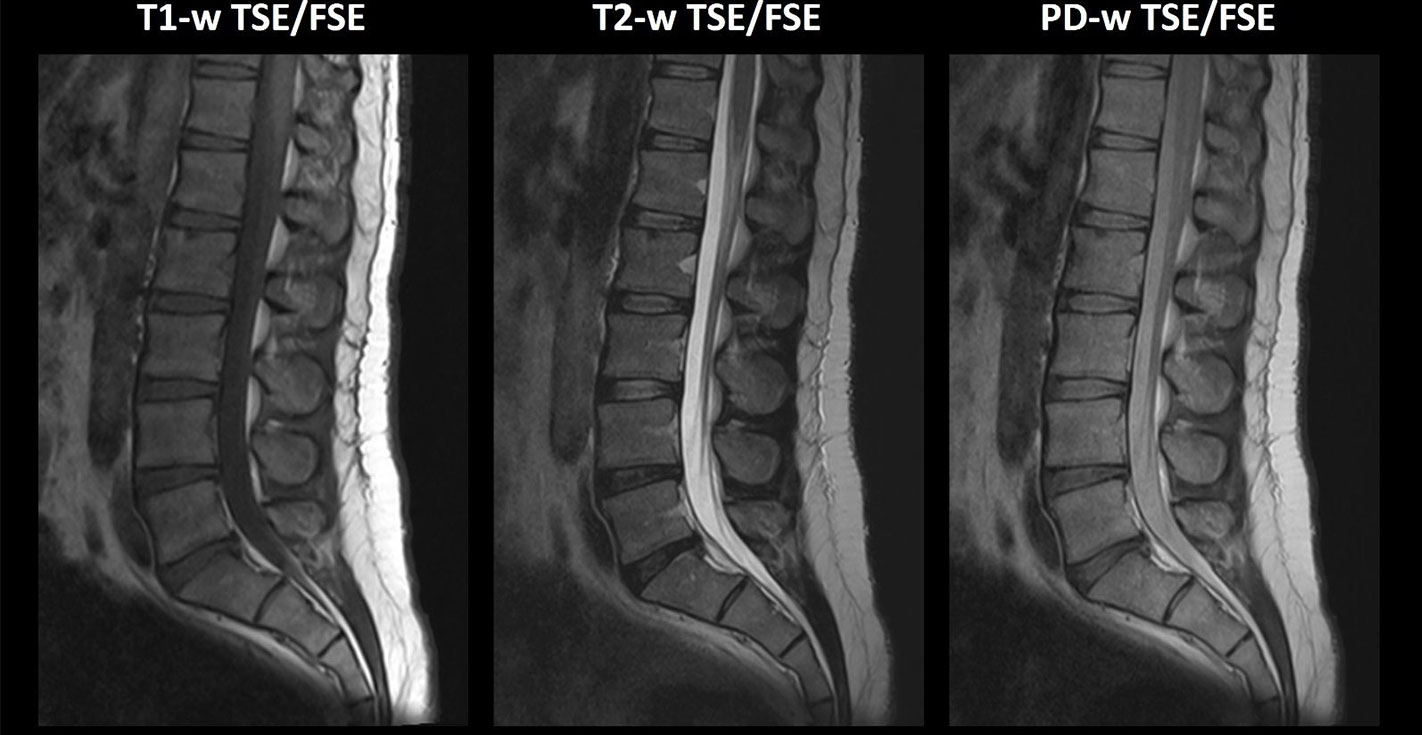

Οβελιαίες τομές ακολουθίας FSE οσφυικής μοίρας σπονδυλικής στήλης βάρους (α) Τ1, (β) Τ2 και (γ) PD